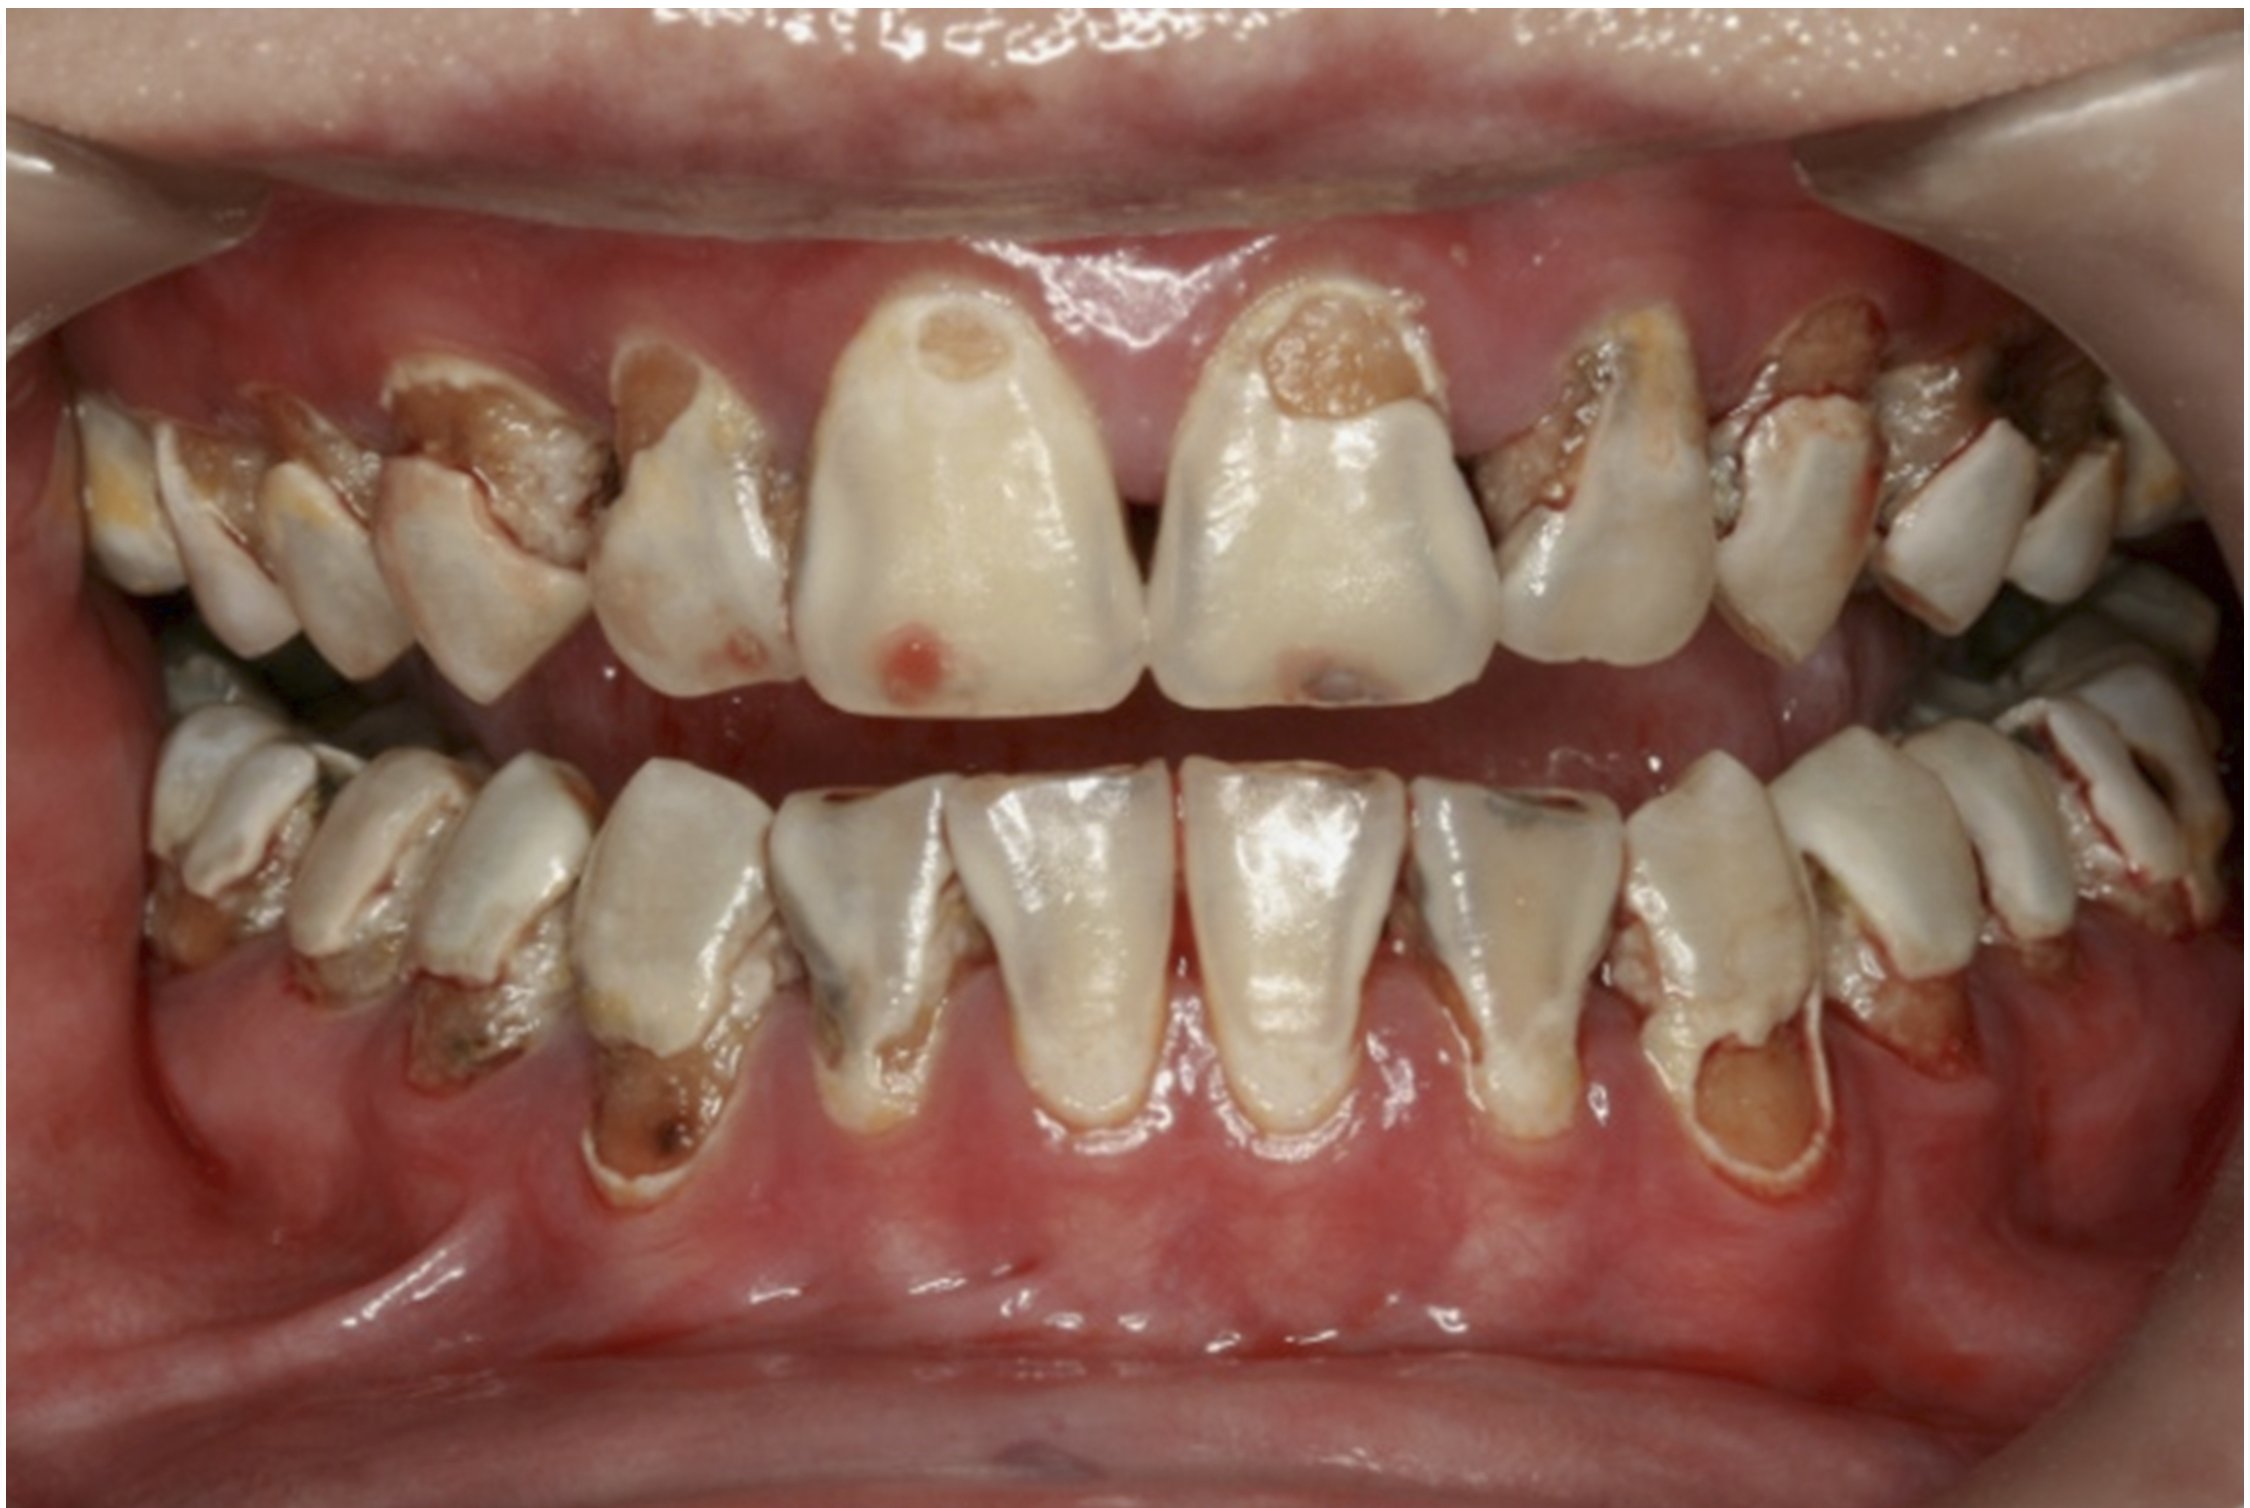

The inherent disadvantage of SDF is that the caries lesions will be stained black after SDF application. SDF stops caries progression by forming a hard, blackened, impermeable layer on the tooth surface that is resistant to caries (Figure 5 through Figure 9). The authors’ clinical observations are that the darker the color, the more likely the caries arrested. Some patients may not be pleased with the esthetics of this treatment outcome; therefore, it is important to inform the patients and parents (for child patients) about this treatment outcome. Moreover, SDF can stain clothes and the skin of the body. Though it does not cause any pain or damage, an SDF stain on skin cannot be easily washed away. It takes around 7 days for it to disappear, and the stain on clothes is permanent.22

There is no consensus on the frequency of application, and 38% SDF has been used annually or biannually on clinical trials in children23,31,33,34 and in elderly.30,35 Yee and his co-worker found one-off application of 12% SDF was ineffective in arresting caries in children.31 The present authors applied 38% SDF weekly for 3 weeks to speed up the process of caries arrest and for treatment of rampant caries.36 One of the present authors’ case reports demonstrated that three weekly applications of 38% SDF can arrest rampant caries and relieve pain from hypersensitivity on a teenager. The SDF-treated caries were found arrested, and they turned coal black in appearance (Figure 9).

Fig 8. Use of 38% SDF to arrest rampant caries in a young teenager: pre-treatment intraoral frontal view of rampant caries. (image from Chu, et al, 2014, ref 36 [reprinted with approval])

Figure 8